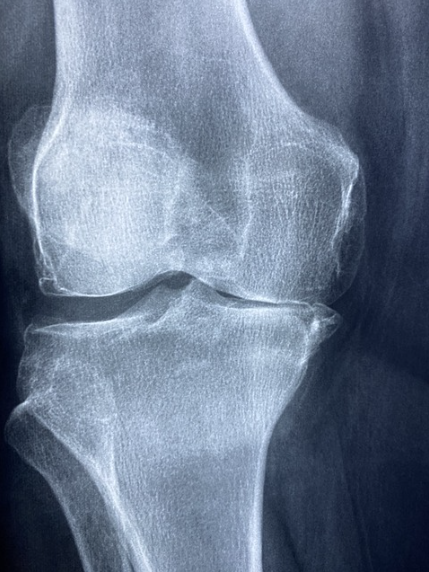

골관절염(Osteroarthritis)는 관절염 중 가장 많은 비중을 차지하는 흔한 관절염입니다. 골관절염의 발병은 주로 관절의 노화로 인한 원인을 통해 발생하며, 신체의 존재하는 관절 중 손, 고관절, 무릎과 같은 부분에 발병이 됩니다.

연골이 일정 수명을 다하여 기능을 잃으면, 뼈와 뼈 간의 마찰을 통해 통증이 발생하며 이때 발병의 사실을 직감하고 병원을 방문하여 판정을 받습니다.

골관절염의 주요 원인으로는 신체의 노화, 무리한 체중의 증가, 과도한 관절의 사용으로 인한 부상, 특정 행동을 통한 관절 부상 등이 주요 원인으로 꼽힙니다.